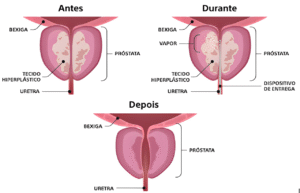

- Ressecção Transuretral da Próstata (RTU):

- Procedimento minimamente invasivo para remover tecido prostático obstrutivo.

- Enucleação Prostática

- Procedimento cirúrgico minimamente invasivo para remover o tecido prostático obstrutivo e melhorar o fluxo urinário.

- Recuperação Rápida: Procedimentos minimamente invasivos têm recuperação mais rápida.

A recuperação varia conforme o tipo de cirurgia. Procedimentos como a RTU e a Enucleção Prostática permitem alta hospitalar no mesmo ou em poucos dias, com retorno rápido às atividades normais. A prostatectomia radical pode exigir uma recuperação mais longa, com acompanhamento contínuo.